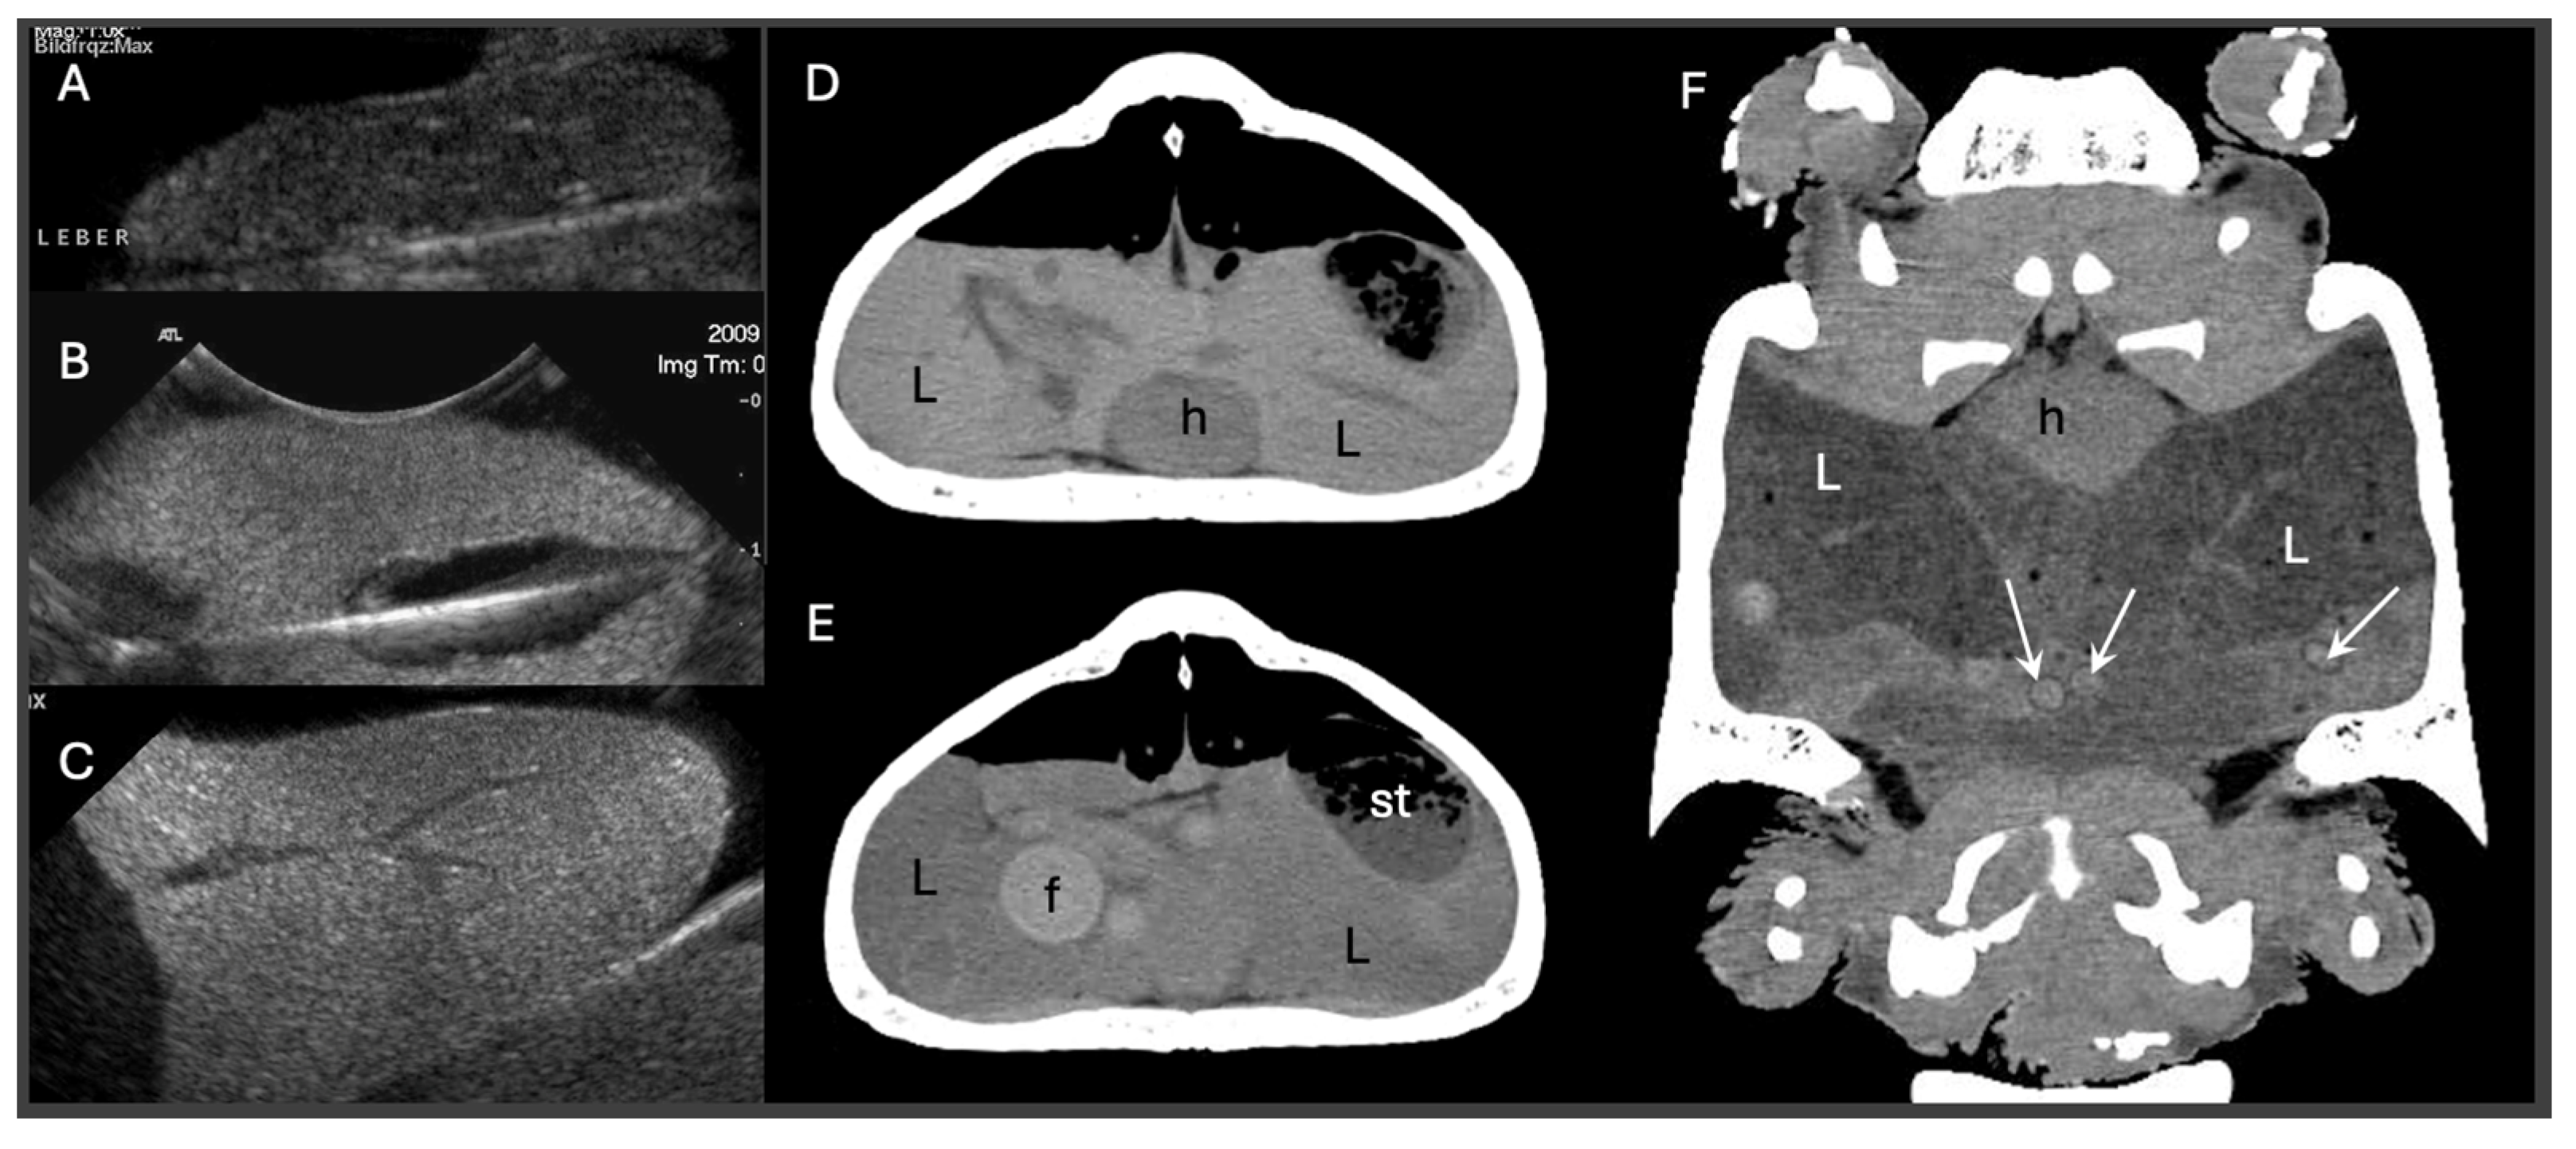

Dystocia, or egg-binding, is a common reproductive emergency in reptiles, often arising from multifactorial systemic and environmental causes. This review focuses on the biochemical and hepatic determinants contributing to dystocia across major reptilian taxa, including lizards, snakes, and chelonians. Prolonged vitellogenesis, hepatic lipidosis, and metabolic disturbances such as hypocalcemia or elevated bile acids may impair oviductal contractility and egg passage, increasing the risk of reproductive failure. The pathophysiology of dystocia is examined with particular emphasis on liver function and its role in reproductive hormone metabolism, nutrient allocation, and systemic homeostasis. Diagnostic strategies, ranging from radiography and ultrasonography to plasma biochemistry, are evaluated for their relevance in assessing reproductive status and perioperative risk. Management options, including medical interventions (e.g., oxytocin protocols, supportive therapy) and surgical techniques (e.g., ovocentesis, coeliotomy, ovariosalpingectomy), are reviewed with consideration of anesthetic safety in metabolically compromised patients. This review aims to inform clinical decision-making by integrating diagnostic and therapeutic approaches with a strong emphasis on hepatic function and biochemical indicators, thereby improving outcomes in the veterinary management of reproductive failure in reptiles.

Dystocia represents a multifactorial and clinically significant reproductive disorder affecting a broad spectrum of reptilian species. Commonly resulting from prolonged vitellogenesis, endocrine disruption, or hepatic lipidosis, dystocia is often exacerbated by suboptimal husbandry or concurrent disease. This review critically evaluates the etiology, diagnostic criteria, and therapeutic interventions associated with this condition. Emphasis is placed on the interplay between metabolic exhaustion and hepatic compromise, which may lower the threshold for surgical intervention. The efficacy and limitations of oxytocin-based protocols are discussed in the context of hormonal receptor variability and response attenuation. Advanced diagnostic modalities, including ultrasonography, radiography/CT, and biochemical profiling, are reviewed for their utility in case stratification. Finally, surgical management options are considered for cases refractory to medical treatment, with attention paid to timing, anesthetic risk, and post-operative care. Collectively, this synthesis aims to inform evidence-based clinical decision-making and promote improved standards of care in reptile reproductive medicine.